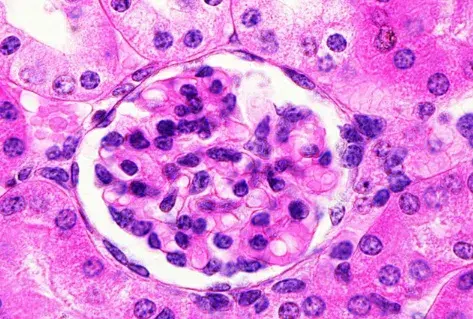

Es posible identificar un glomérulo con rotura de la membrana basal glomerular, con crecimiento celular en el espacio de Bowman (flecha blanca), células gigantes multinucleadas (estrella) y ruptura de la cápsula de Bowman (flecha negra) (tinción PAS; 400×). PAS, ácido periódico-Schiff.

La biopsia renal reveló GN (glomerulonefritis) crescéntica necrotizante difusa sin hipercelularidad endocapilar. Algunos raros glomérulos contenían células gigantes multinucleadas.

La evaluación de la microscopía de luz puede ayudar en la diferenciación entre casos de **GN por anti-MBG** y casos de **GN-ANCA**, ya que en la GN por anti-MBG no se observa hipercelularidad endocapilar y se puede identificar la presencia de células gigantes multinucleadas. Estas células gigantes multinucleadas resultan de la naturaleza explosiva y la rápida destrucción de los glomérulos observada en la anti-MBG.